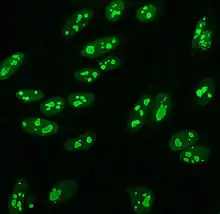

Crithidia luciliae

Crithidia luciliae are haemoflaggelate single celled protists. They are used as a substrate in immunofluorescence for the detection of anti-dsDNA antibodies. They possess an organelle known as the kinetoplast which is a large mitochondrion with a network of interlocking circular dsDNA molecules. After incubation with serum containing anti-dsDNA antibodies and fluorescent-labelled anti-human antibodies, the kinetoplast will fluoresce. The lack of other nuclear antigens in this organelle means that using C. luciliae as a substrate allows for the specific detection of anti-dsDNA antibodies.[8][59][60]